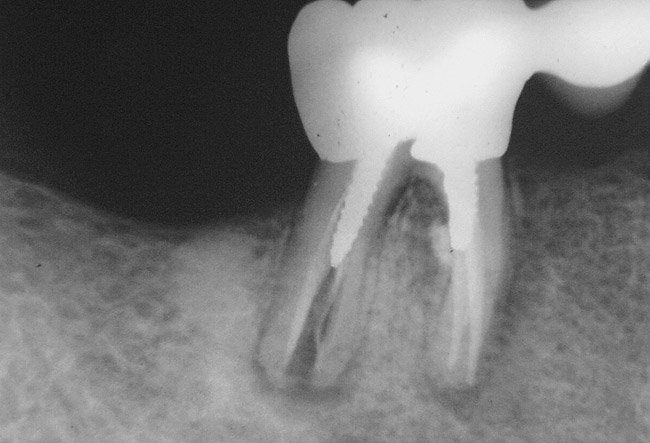

Many times, endodontically treated teeth are compromised in their overall remaining coronal structure because of caries, previous restorations, trauma, and the endodontic access. Reeh et al evaluated reduction in tooth stiffness as a result of endodontic and restorative procedures.19 They found that the tooth was inherently stiff and resistant to flexion. Once a tooth was prepared, the rigidity of the tooth was reduced. An occlusal cavity preparation reduced tooth stiffness by 20%, and loss of marginal ridge integrity with a mesial-occlusal-distal preparation reduced cuspal stiffness by 63%. In comparison, an endodontic access preparation reduced relative tooth stiffness by a mere 5%. Other studies have confirmed that the loss of tooth structure makes endodontically treated teeth more susceptible to fracture.20-22 Some practitioners believe that posts placed in the restoration of an endodontically treated tooth reinforce that tooth.7 Research studies have demonstrated that metal posts, both prefabricated and cast, may in fact lead to root fracture (Figure 1A and Figure 1B).23-25

Figure 1a  Mandibular first molar with distal root fracture. Note the root canal perforation and post in the mesial root.

Figure 1a

Figure 1b  Mandibular second premolar with a short, large-diameter post that has created a vertical root fracture.

Figure 1b